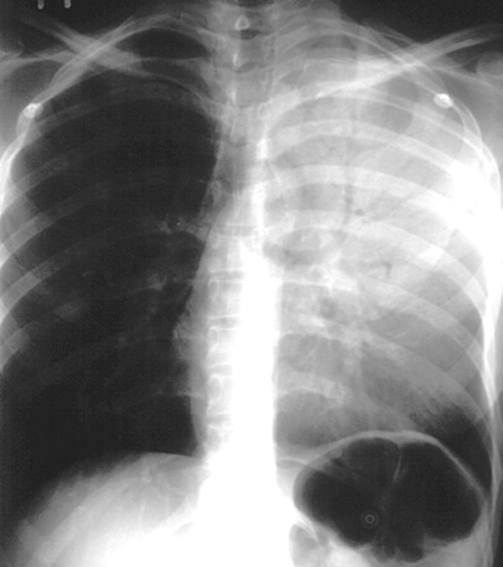

Pleural effusion with tracheal deviation